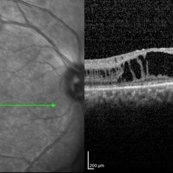

Central Areolar Choroidal Dystrophy Central Areolar Choroidal DystrophyJul 7 2015 by Hamid Ahmadieh, MD OCT images of both eyes of a 58-year-old man with progressive loss of vision. VA OD is 20/60 and VA OS is 20/400. Photographer: Soulmaz Shahmohammad, Negah Eye Center, Tehran, Iran Imaging device: Specteralis Condition/keywords: central areolar choroidal dystrophy (CACD), optical coherence tomography (OCT)